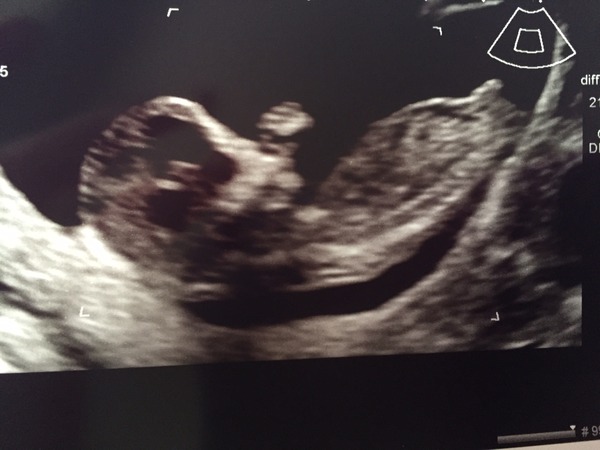

Scan all good

she didn't manage to get a proper NT measurement though, when she tried it came up as 1.4 but she said she couldn't put it in full confidence so would send me for blood tests at 15 weeks instead.

Measured as due date 4th September (7 week scan put it at 6th and LMP at 9th!) I think I must be growing a giraffe in there...

Very sleepy baby, refused to move much even when she asked me to jiggle around lots but eventually waved at us right at the end - the sonographer reckoned baby was picking it's nose